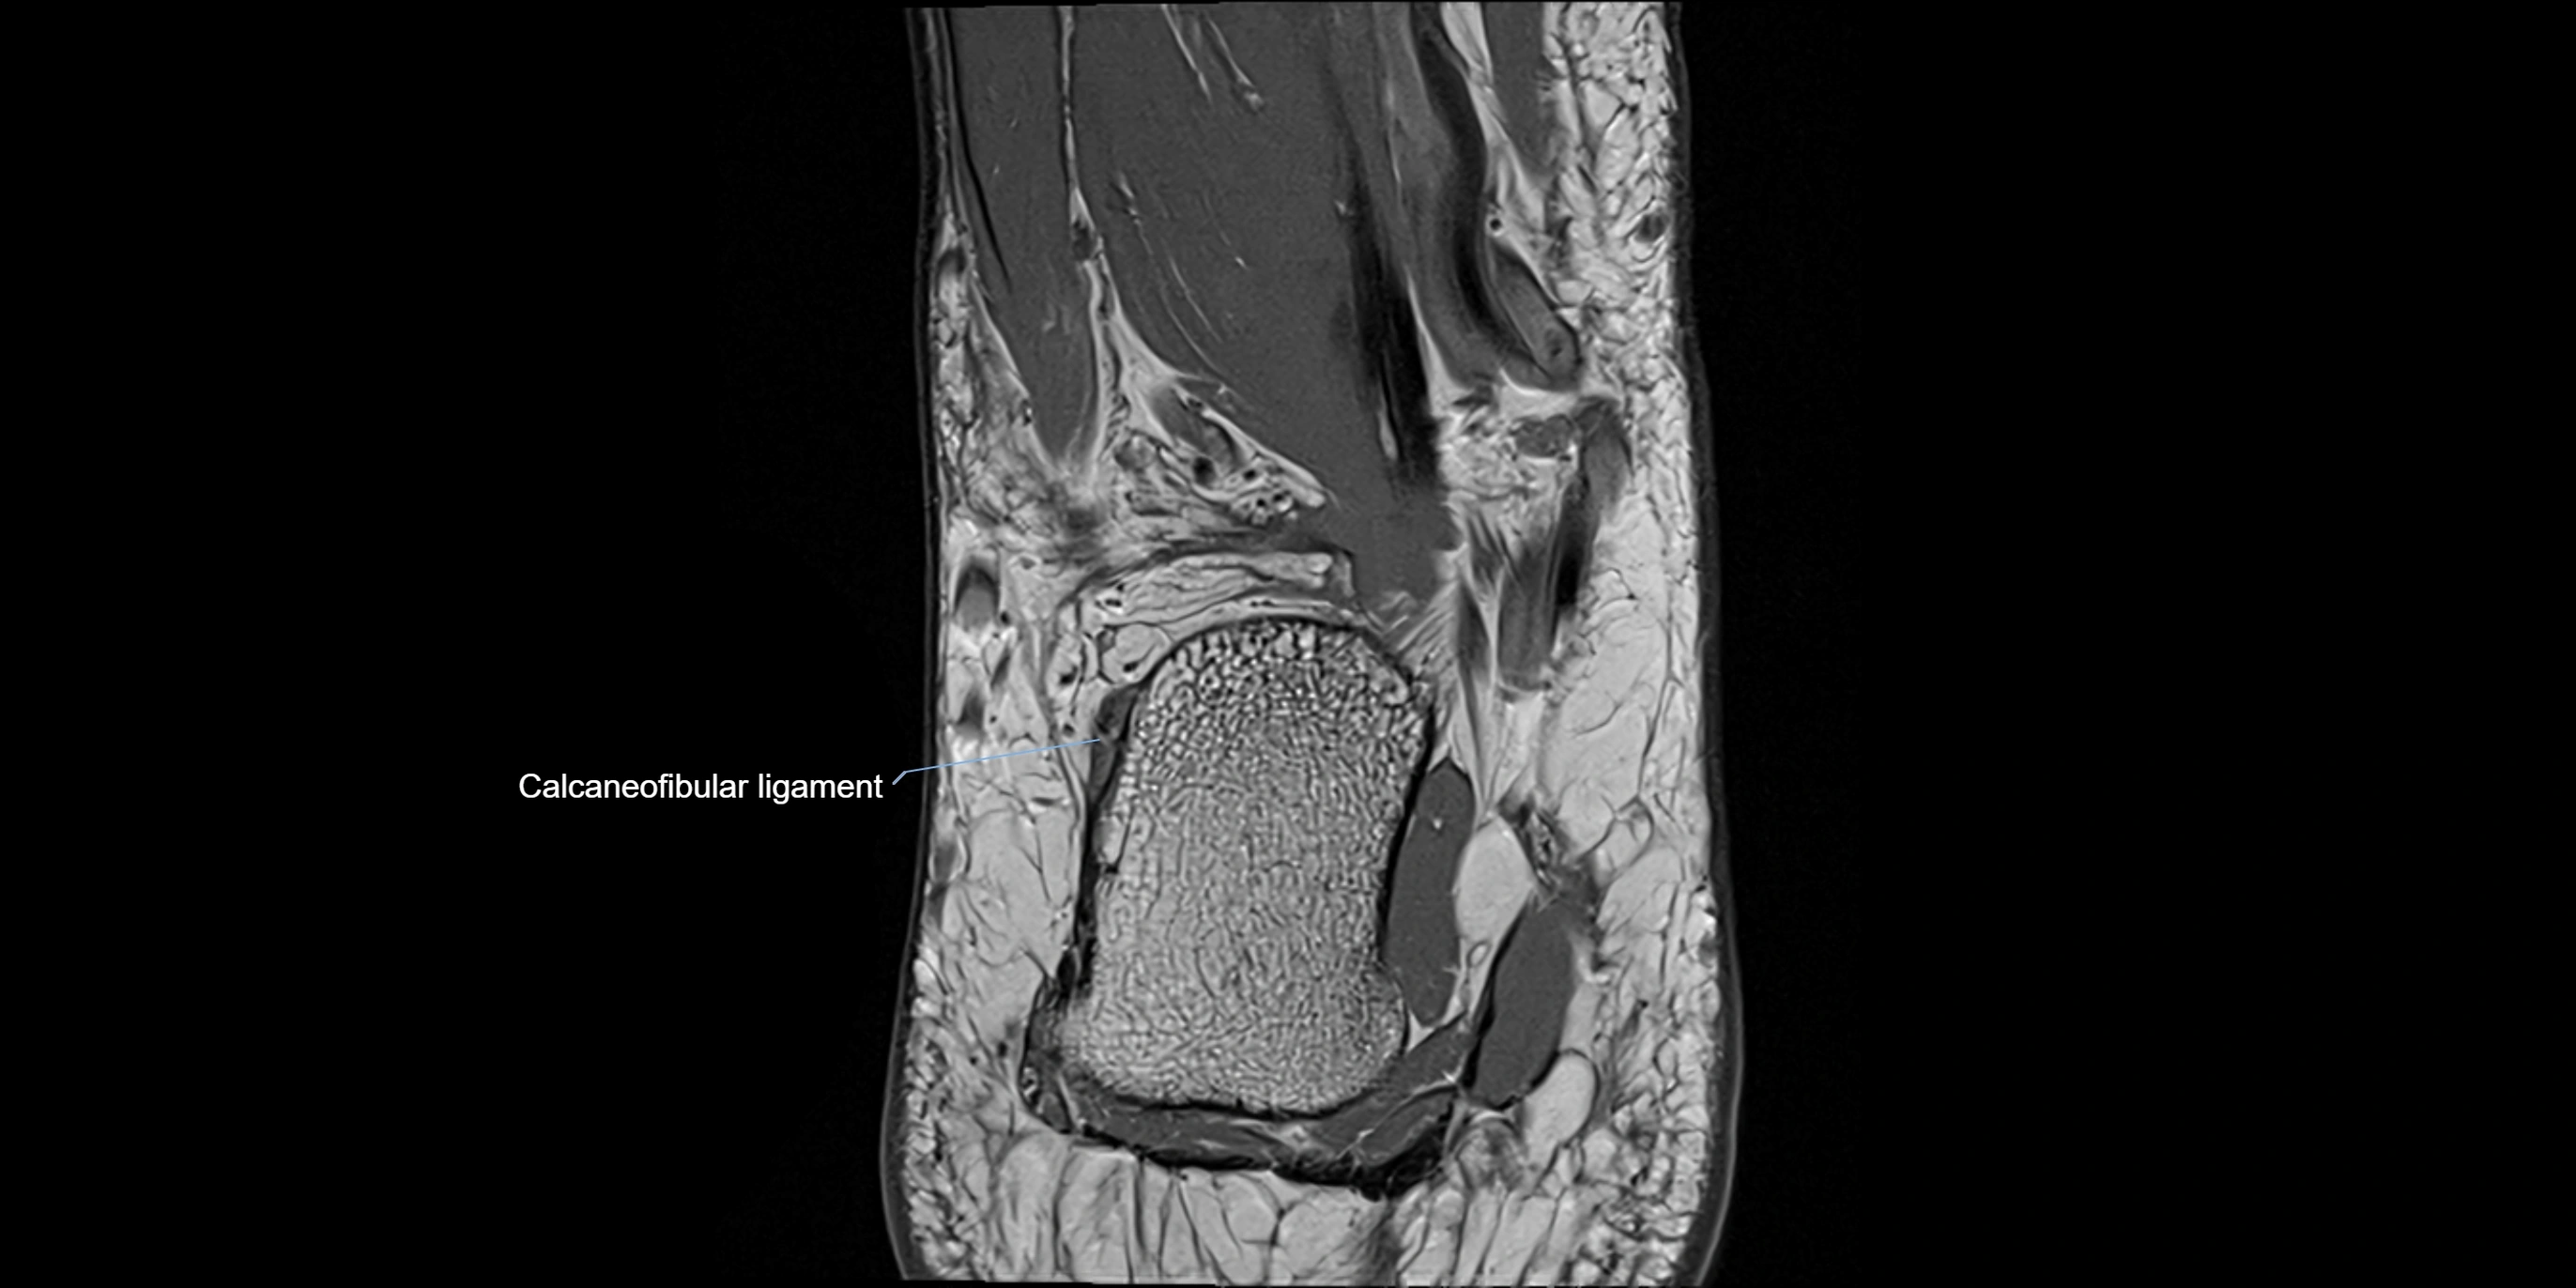

MRI image

image